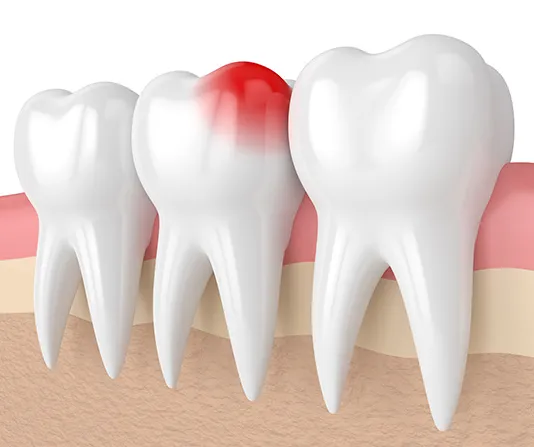

Dental implants are a long-term solution that feels and functions like a natural tooth. The implant is placed in the jawbone where it bonds with the bone, creating a secure foundation for a custom crown. Implants help maintain bone strength, improve chewing ability, and restore the appearance of your smile. With the right care, they can last for many years.